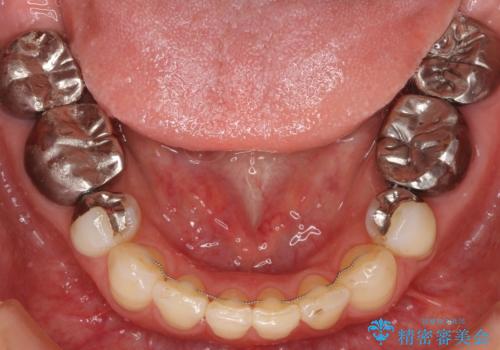

歯ぎしりで擦り減った歯をクラウンに補綴

- 顎が痛いことを主訴に来院されました。

夜間のナイトガードを作製しました。

右下に装着されているインレーが歯ぎしりによって適合が悪く穴が開いている状態であったため、インレー、虫歯を除去しクラウンを装着しました。

インレー(詰め物)が装着されている歯に対して、歯ぎしりなどの強い力がかかると歯とインレーの固さの違いから境目の部分に段差が生まれ、そこから虫歯や脱離の原因となる場合があります。

今回のケースでは歯の量が少なく破折等のリスクがあったためクラウン(被せ物)で補綴しまし、夜間にナイトガードを使用しています。